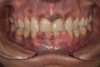

Fig 11. Postoperative frontal smile view.

Figure 11

A few weeks later, the facial veneers were bonded directly to the underlying enamel. A postoperative photograph (Figure 11) revealed the restored harmony of the patient’s smile and the occlusal contacts in MIP (Figure 12). The palatal surfaces restored with nanofilled composite resin developed good anterior guidance that was harmonized to the patient’s chewing cycle (Figure 13 and Figure 14).19